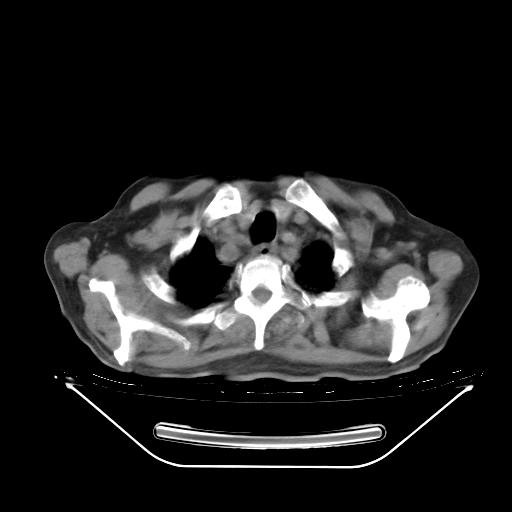

今天复查肺部CT,发现双肺广泛磨玻璃样改变。所以我把3月19日和5月9日相隔50天的肺部CT上传。请大家会诊。

2009年3月19日肺部CT片。

2009年3月19日肺部CT